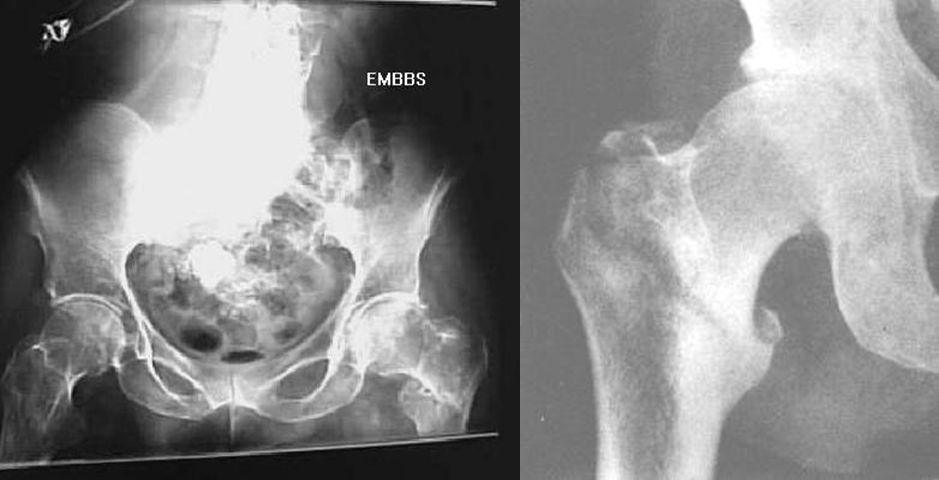

先天性髋脱位

疼痛科怎么理疗疼痛科医生、康复理疗科医生、针刀针灸医生应掌握的常见骨科疾病X光片_https://www.jmylbn.com_新闻资讯_第52张